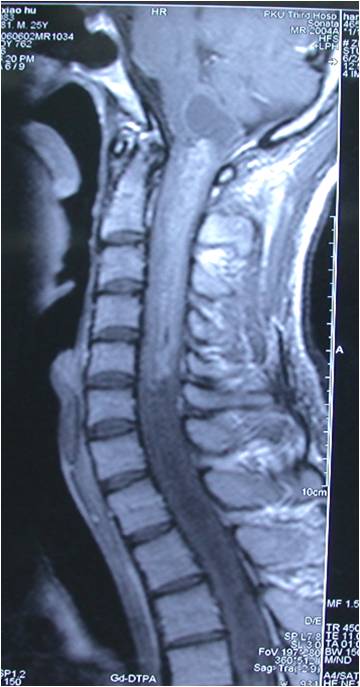

术前MRI见肿瘤位于高颈段髓内